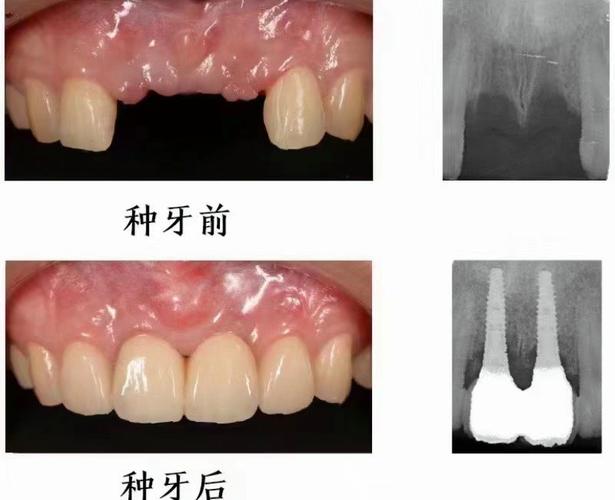

种植牙的原理是通过外科手术将纯钛种植体植入牙槽骨内,作为人工牙根,待其与骨组织结合(骨结合)后,再安装基台和牙冠,实现功能与美观的恢复,全口无牙患者能否种牙,核心取决于牙槽骨的条件——包括骨量(高度、宽度、密度)、骨质量以及是否有影响愈合的全身因素。

对于骨量充足、无严重炎症的患者,可在拔牙后立即植入种植体(即刻种植),甚至结合数字化导板技术,实现“当天种牙、当天戴牙”(即刻负重),避免传统种植需等待3-6个月骨结合的漫长周期,但需严格评估适应证,并非所有患者都能适用。

| 基台与牙冠安装 | 二次手术(若需)暴露种植体,安装基台,取模制作牙冠(全瓷/烤瓷牙冠) | 2-3周 |

- 保护牙槽骨:种植体刺激牙槽骨,延缓吸收,避免面部塌陷。